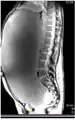

Imaging

-

MRI giant serous cystadenoma of ovary -

MRI giant serous cystadenoma ovary